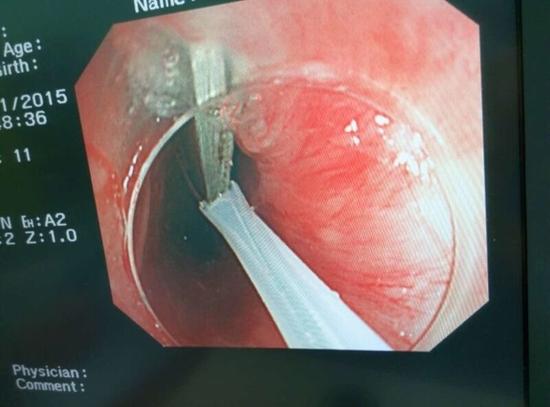

醫(yī)生從華先生胃里取出的鑷子和打火機(jī)

隨后,范醫(yī)生先用圈套器套取出了長(zhǎng)10厘米的鑷子,再一個(gè)一個(gè)地取出了打火機(jī)。整個(gè)取出過(guò)程小心謹(jǐn)慎而又一氣呵成,只用了不到10分鐘。